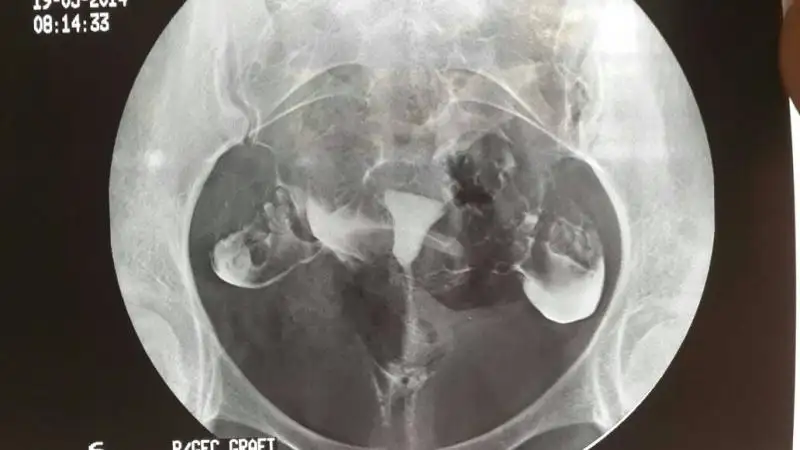

Benimki de bu sekilde raporda rahimin normal form ve hacimde oldugu verilen maddenin tuplerden serbest olarak dagildigi tuplerin normal capta oldugu herhangi bir patolojik bulgu saptanmadgi yaziyr

Senin film çok kaliteli yalnız.. Bende de su yazıyor madde sol tubadan geçip peritonaya ulaştı sağda madde geçişi azaldı..